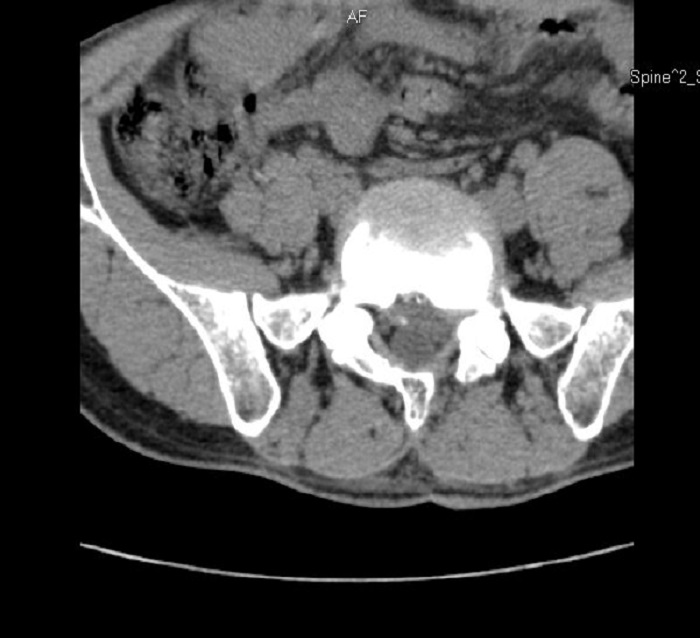

术后

术前